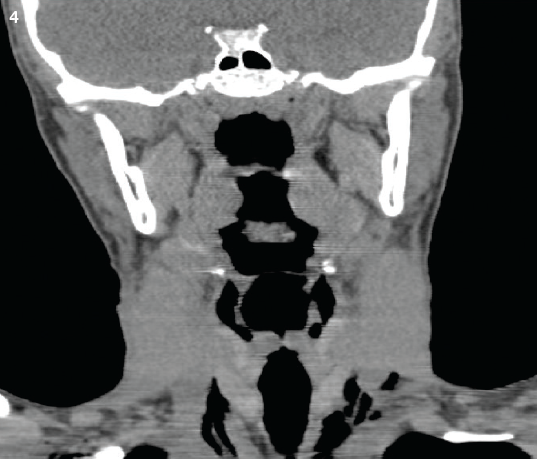

Radiographs (Figures 1 and 2) and computed tomography (CT) scans of the chest and neck were ordered (Figures 3 and 4) and confirmed pneumomediastinum but failed to identify an etiology. Because spontaneous pneumomediastinum is uncommon, the patient was admitted to the pediatric floor for further workup and evaluation. Otolaryngology was consulted.

Figure 4. A sagittal CT scan of the neck showed the presence of air in the paratracheal space.